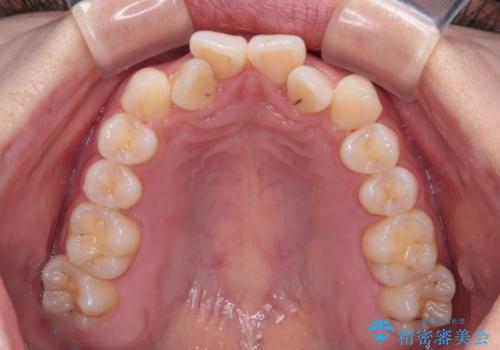

前歯のクロスバイト 裏側に隠れた歯をワイヤー装置で短期間治療

- 上顎前歯のクロスバイトを気にして来院された患者様です。

ワイヤー矯正でもマウスピース矯正でも対応可能でしたが、マウスピースによる自己管理に一切の自信がないとのことで、ワイヤー装置にて矯正治療を行うこととしました。

装置の外見を気にしていましたが、短期間で治療を終えることができるだろうと伝えると、安価であるメタルブラケットを選択されました。

想定通り、1年強で綺麗に仕上げることができました。